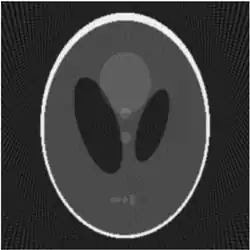

In the two-dimensional case, the most commonly used analytical formula to recover from its Radon transform is the Filtered Back-projection Formula or Radon Inversion Formula[9]: where is such that .[9] The convolution kernel is referred to as Ramp filter in some literature.

Explicit and computationally efficient inversion formulas for the Radon transform and its dual are available. The Radon transform in dimensions can be inverted by the formula:[11] where , and the power of the Laplacian is defined as a pseudo-differential operator if necessary by the Fourier transform: For computational purposes, the power of the Laplacian is commuted with the dual transform to give:[12] where is the Hilbert transform with respect to the s variable. In two dimensions, the operator appears in image processing as a ramp filter.[13] One can prove directly from the Fourier slice theorem and change of variables for integration that for a compactly supported continuous function of two variables: Thus in an image processing context the original image can be recovered from the 'sinogram' data by applying a ramp filter (in the variable) and then back-projecting. As the filtering step can be performed efficiently (for example using digital signal processing techniques) and the back projection step is simply an accumulation of values in the pixels of the image, this results in a highly efficient, and hence widely used, algorithm.

Compared with the Filtered Back-projection method, iterative reconstruction costs large computation time, limiting its practical use. However, due to the ill-posedness of Radon Inversion, the Filtered Back-projection method may be infeasible in the presence of discontinuity or noise. Iterative reconstruction methods (e.g. iterative Sparse Asymptotic Minimum Variance[10]) could provide metal artefact reduction, noise and dose reduction for the reconstructed result that attract much research interest around the world.